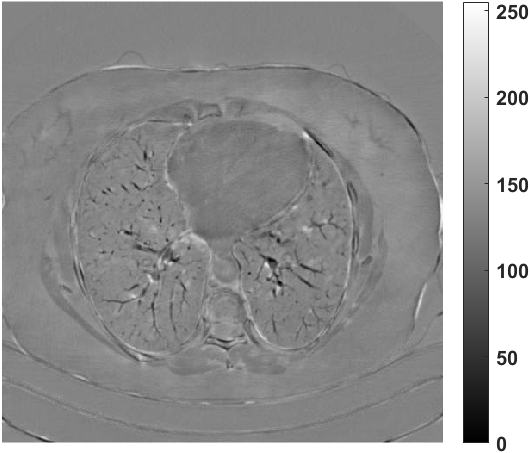

Fig. 4 presents the reconstruction results and residual images obtained by different methods for limited-angle reconstruction. As can be seen, the learning-based methods outperform the direct method and TV model, which exhibit serious artifacts in the missing angle region. Although the denoiser introduced by the FBP-Unet can somehow deal with the noises, the result still presents obvious artifacts. Compared to the SIPID, PD-net and FSR-nets, our LRIP-net1/2 can better preserve the image details and edges with less information left in the residual images. Thus, both the quantitative and qualitative results confirm that the low-to-high double-resolution strategy can improve the reconstruction accuracy for the limited-angle reconstruction problem.

We observe that the low-resolution image prior plays an important role in our method. More specifically, we compare the results of our LRIP-net with respect to different low-resolution priors, which are obtained by down-sampling rate of 1/2, 1/4, and 1/8, respectively. As can be seen in Table III, the best reconstruction results are obtained with the image prior reconstructed by the down-sampling rate of for 150∘, 120∘ and 90∘ limited-angle reconstruction. The visual comparison based on different image priors are also provided in Fig. 5, where obviously less artifacts are left in the reconstruction image by LRIP-net1/8. By comparing the running time, it is easy to see that the smaller the low-resolution image prior, the faster the LRIP-net works.